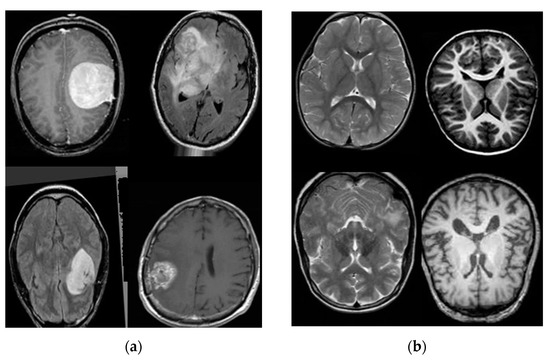

3. Databases

3.1. Database Collection